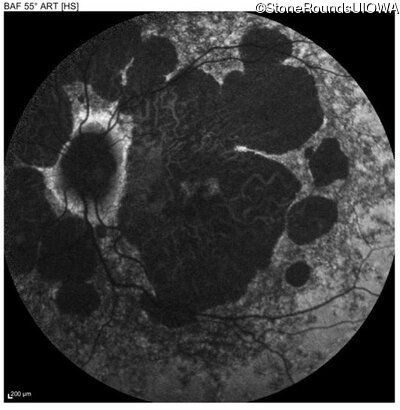

AR Stargardt Disease (IIA)

Age at visit: 51 years

This 51 year old woman first experienced some abnormality in her distance vision when she was 27 years old. She feels that her vision has been stable since that time.

Diagnosis & molecular findings

Disease Gene Allele 1 variant(s) Allele 2 variant(s) Inheritance mode

AR Stargardt Disease ABCA4 Gly1507Arg GGG>AGG IVS42+1 G>A AR